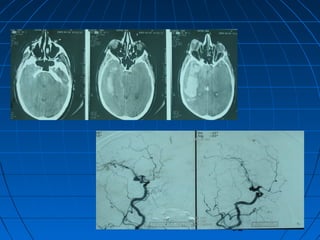

 S.Ç.: 32 yaşında kadın hastaS.Ç.: 32 yaşında kadın hasta

 Ani şiddetli başağrısı, B-KAni şiddetli başağrısı, B-K

CERRAHİCERRAHİ

 Sol frontoparyetal geniş kranyotomiSol frontoparyetal geniş kranyotomi

 AVM’nin total rezeksiyonuAVM’nin total rezeksiyonu

87

88